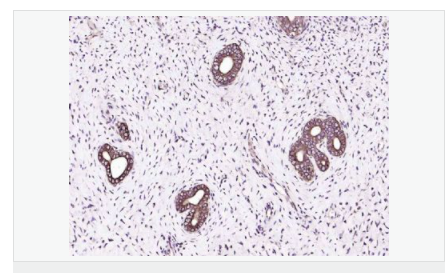

| 产品应用 | WB=1:500-2000 ELISA=1:5000-10000 IP=1:20-100 IHC-P=1:100-500 IHC-F=1:100-500 IF=1:100-500 (石蜡切片需做抗原修复) not yet tested in other applications. optimal dilutions/concentrations should be determined by the end user. |

| 免 疫 原 | KLH conjugated synthetic peptide derived from human IGF-1:49-100/195 |